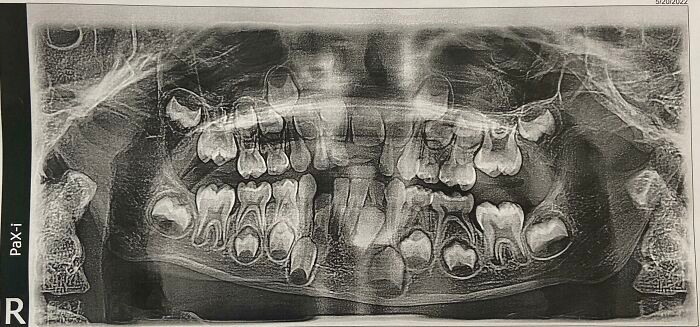

Jakarta - Lihat deretan foto kondisi tubuh manusia paling ekstrem dan langka yang bikin takjub sekaligus merinding. Nyata, aneh, dan sulit dipercaya!

Kondisi Tubuh Manusia Ini Bikin Takjub dan Merinding